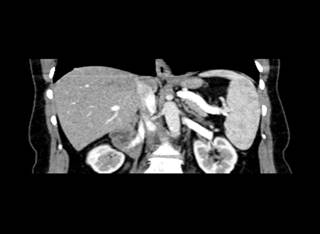

of the lung parenchyma was noted. In the abdominal cavity, the CT revealed

hepatosplenomegaly Figure 2 and a lesion in the eighth

hepatic segment (hemangioma). The portal vein diameter was estimated to be 16

mm, the spleen vein diameter 15 mm, and the superior mesenteric vein 11 mm.

Figure 2

|

Figure 2 Coronal View of the Hepatosplenomegaly from the Contrast-Enhanced CT |